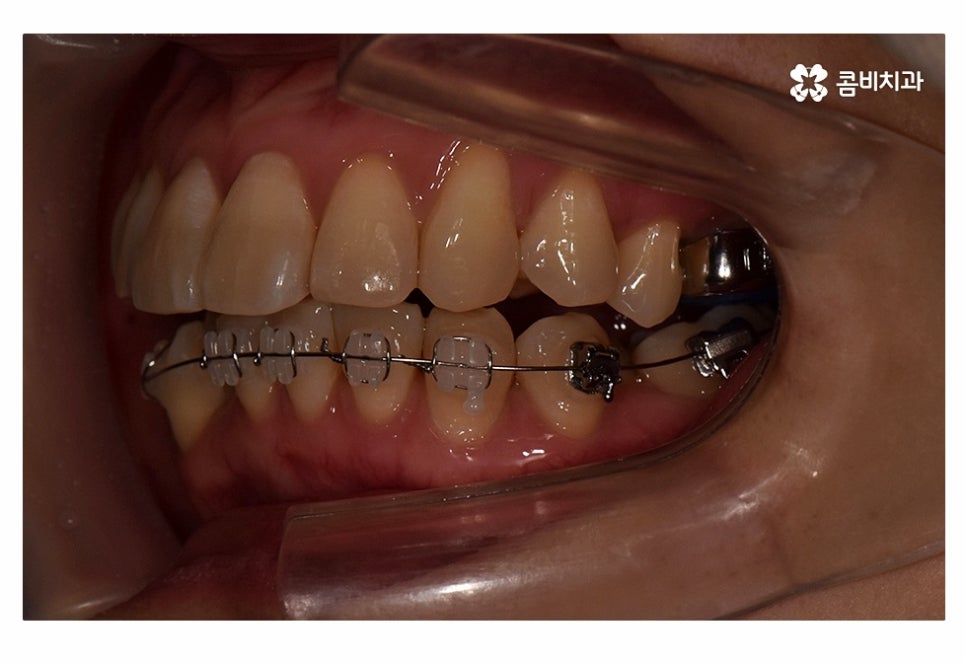

오늘 보실 교정 사례 역시도 윗니는 치아 설측교정으로

진행이 되고 아랫니는 일반적인 순측교정으로 진행되었으며

이러한 치아교정 방법을 콤비교정이라고 부르고 있어요.

아랫니의 경우 순측으로 장치를 부착하였고 아랫니의 경우

순측으로 장치를 부착해도 크게 웃지 않는 이상 잘 보이지 않기 때문에

위 환자분처럼 윗니만 치아설측교정으로 진행을 하고 아랫니는

순측으로 진행하는 경우가 많이 있어요.